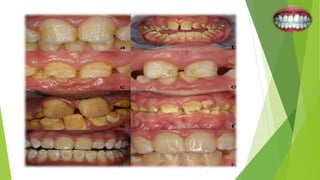

Type 2: Hypomaturation Amelogenesis Imperfecta

 Occurs during matrix apposition.

 Enamel is softer and chips from the underlying dentin.

 Enamel has a mottled brown-yellow-white color.

 Contact points present as enamel is of normal thickness.

 Radiographically enamel approaches the radio density of dentin.

Type 3: Hypocalcified Amelogenesis Imperfecta

 Occurs during the calcification stage.

 Most common type.

 Enamel is of normal thickness but soft, friable, and easily lost by attrition.

 Enamel appears dull, lustrous, honey colored and stains easily.